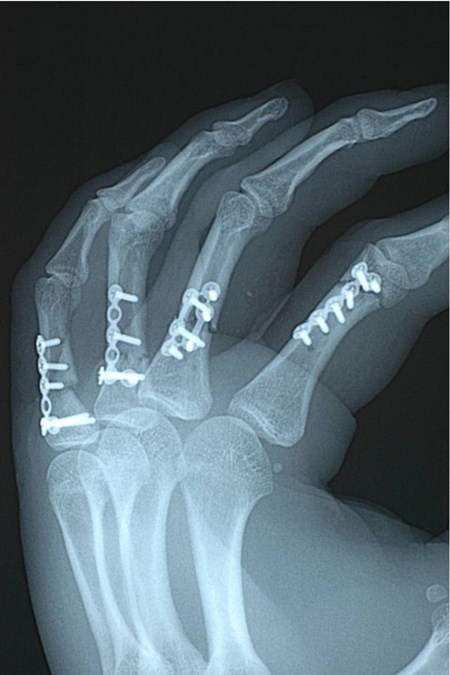

= fracturen van middenhandsbeentjes en vingerfracturen

Is de breuk niet stabiel genoeg of teveel verplaatst om tot een goede heling te komen is operatief ingrijpen noodzakelijk, dit kan gebeuren door plaat osteosynthese, pinfixatie of uitwendige fixatie.